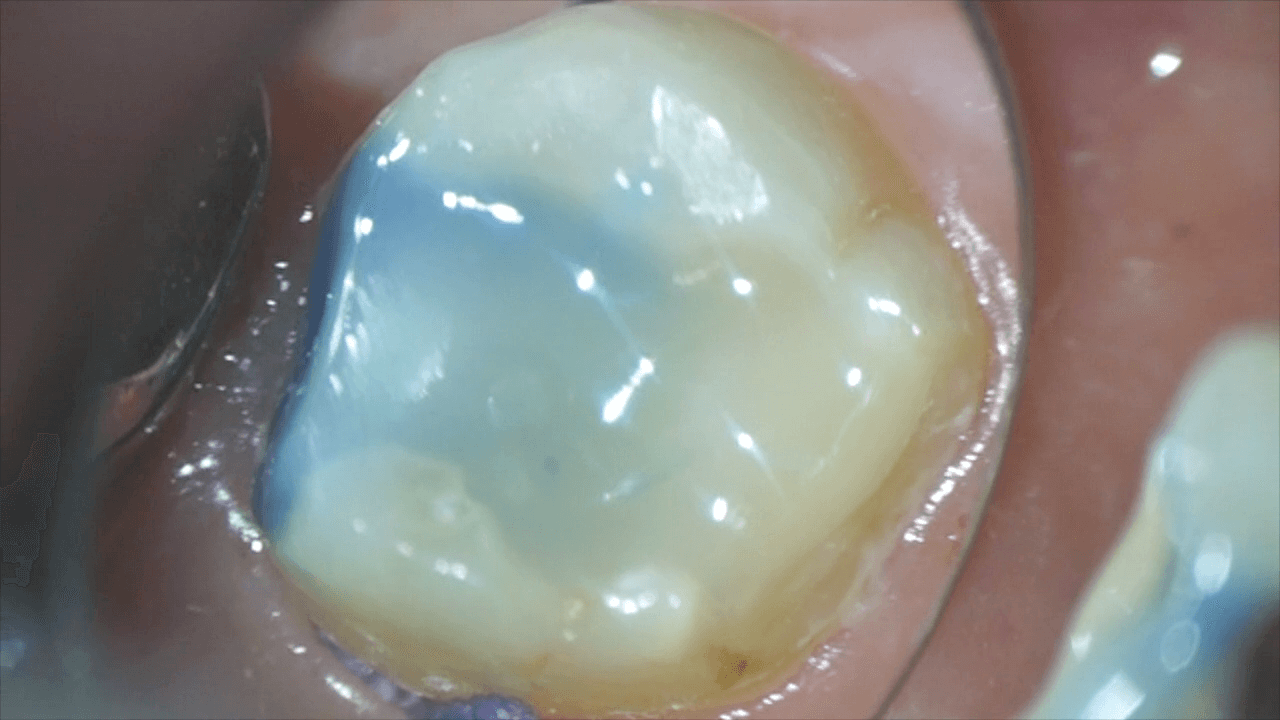

その後、新たにコンポジットレジンで土台を建てました。

これらは、マイクロスコープを用いた精密治療により行いました。

今後、この歯は、残っている量が少ないため、かぶせます。量が中途半端に残っている歯に再度つめ物をしても、また問題が起こる可能性が高いため、歯の補強を目的として、クラウンにします。